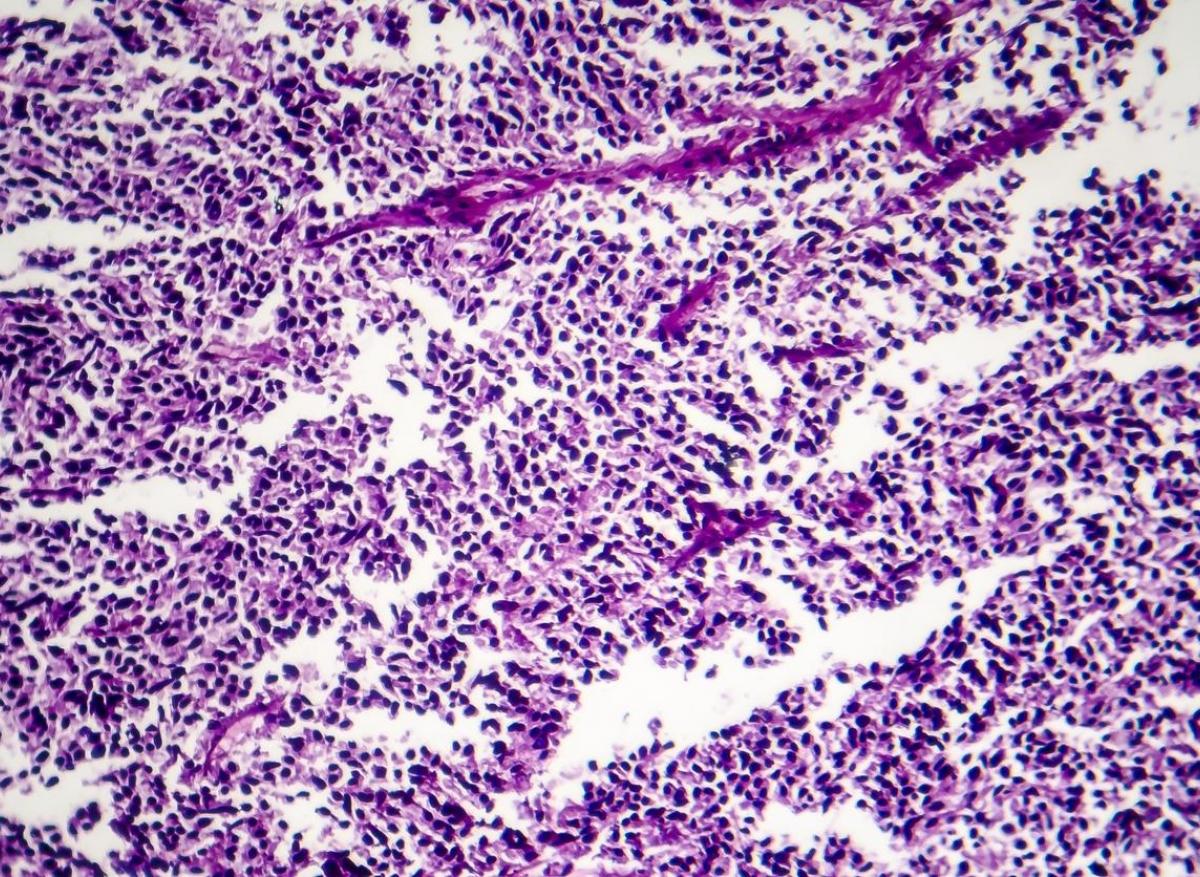

Le cancer du poumon à petites cellules (CPPC) n’est pas le sous-type le plus fréquent (15%), mais c’est le plus agressif, et il est caractérisé par une prolifération et des métastases rapides. Les patients atteints de CPPC ont généralement une maladie avancée au moment du diagnostic avec un taux de survie à 5 ans de 7%. Depuis les années 1990, le traitement standard de première intention pour le CPPC au stade étendu reste la chimiothérapie avec un agent à base de platine et l'étoposide, offrant une survie globale médiane d'environ 10 mois, une survie qui a été modestement améliorée par les anti-PDL1.